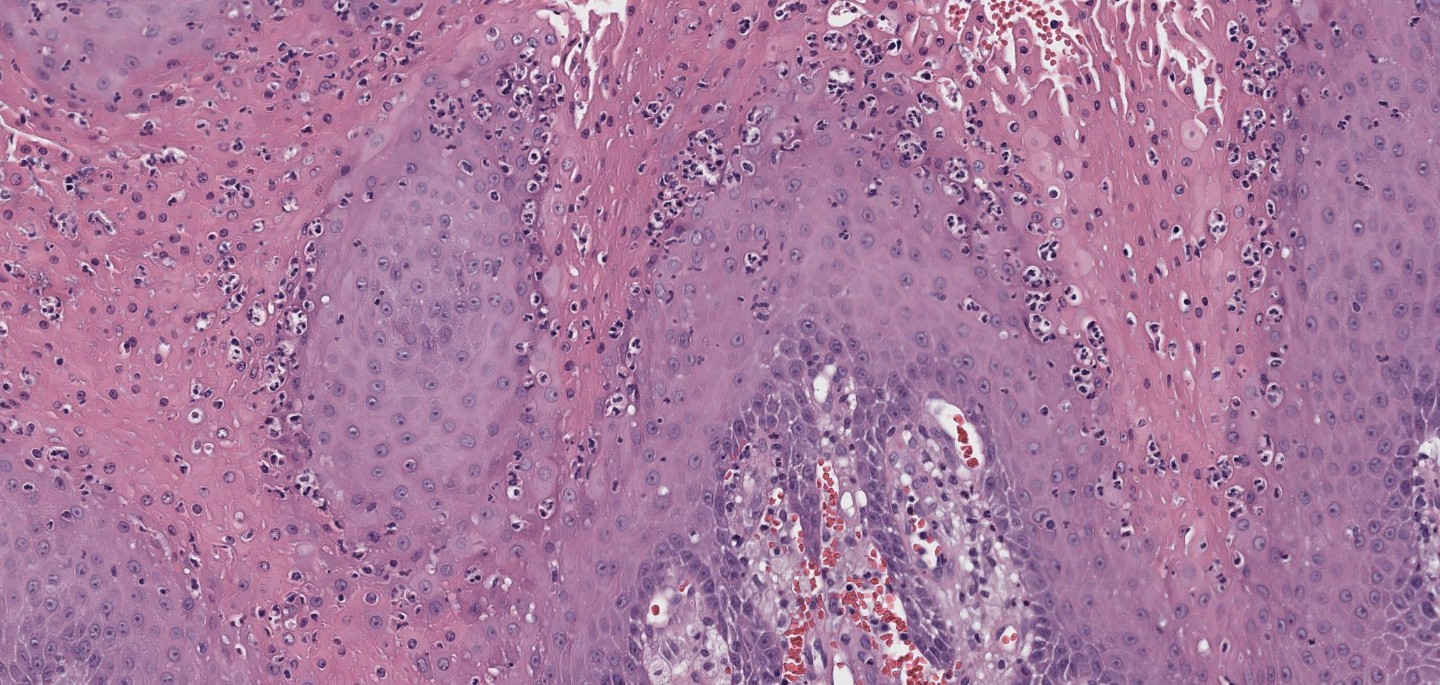

(High power showing parakeratosis and neutrophils)

(High power showing foamy macrophages in dermal papillae)

The presence of foamy macrophages (lipid-laden histiocytes) within dermal papillae is diagnostic. This lesion is not associated with HPV, setting it apart from other verrucous lesions in the anogenital region.